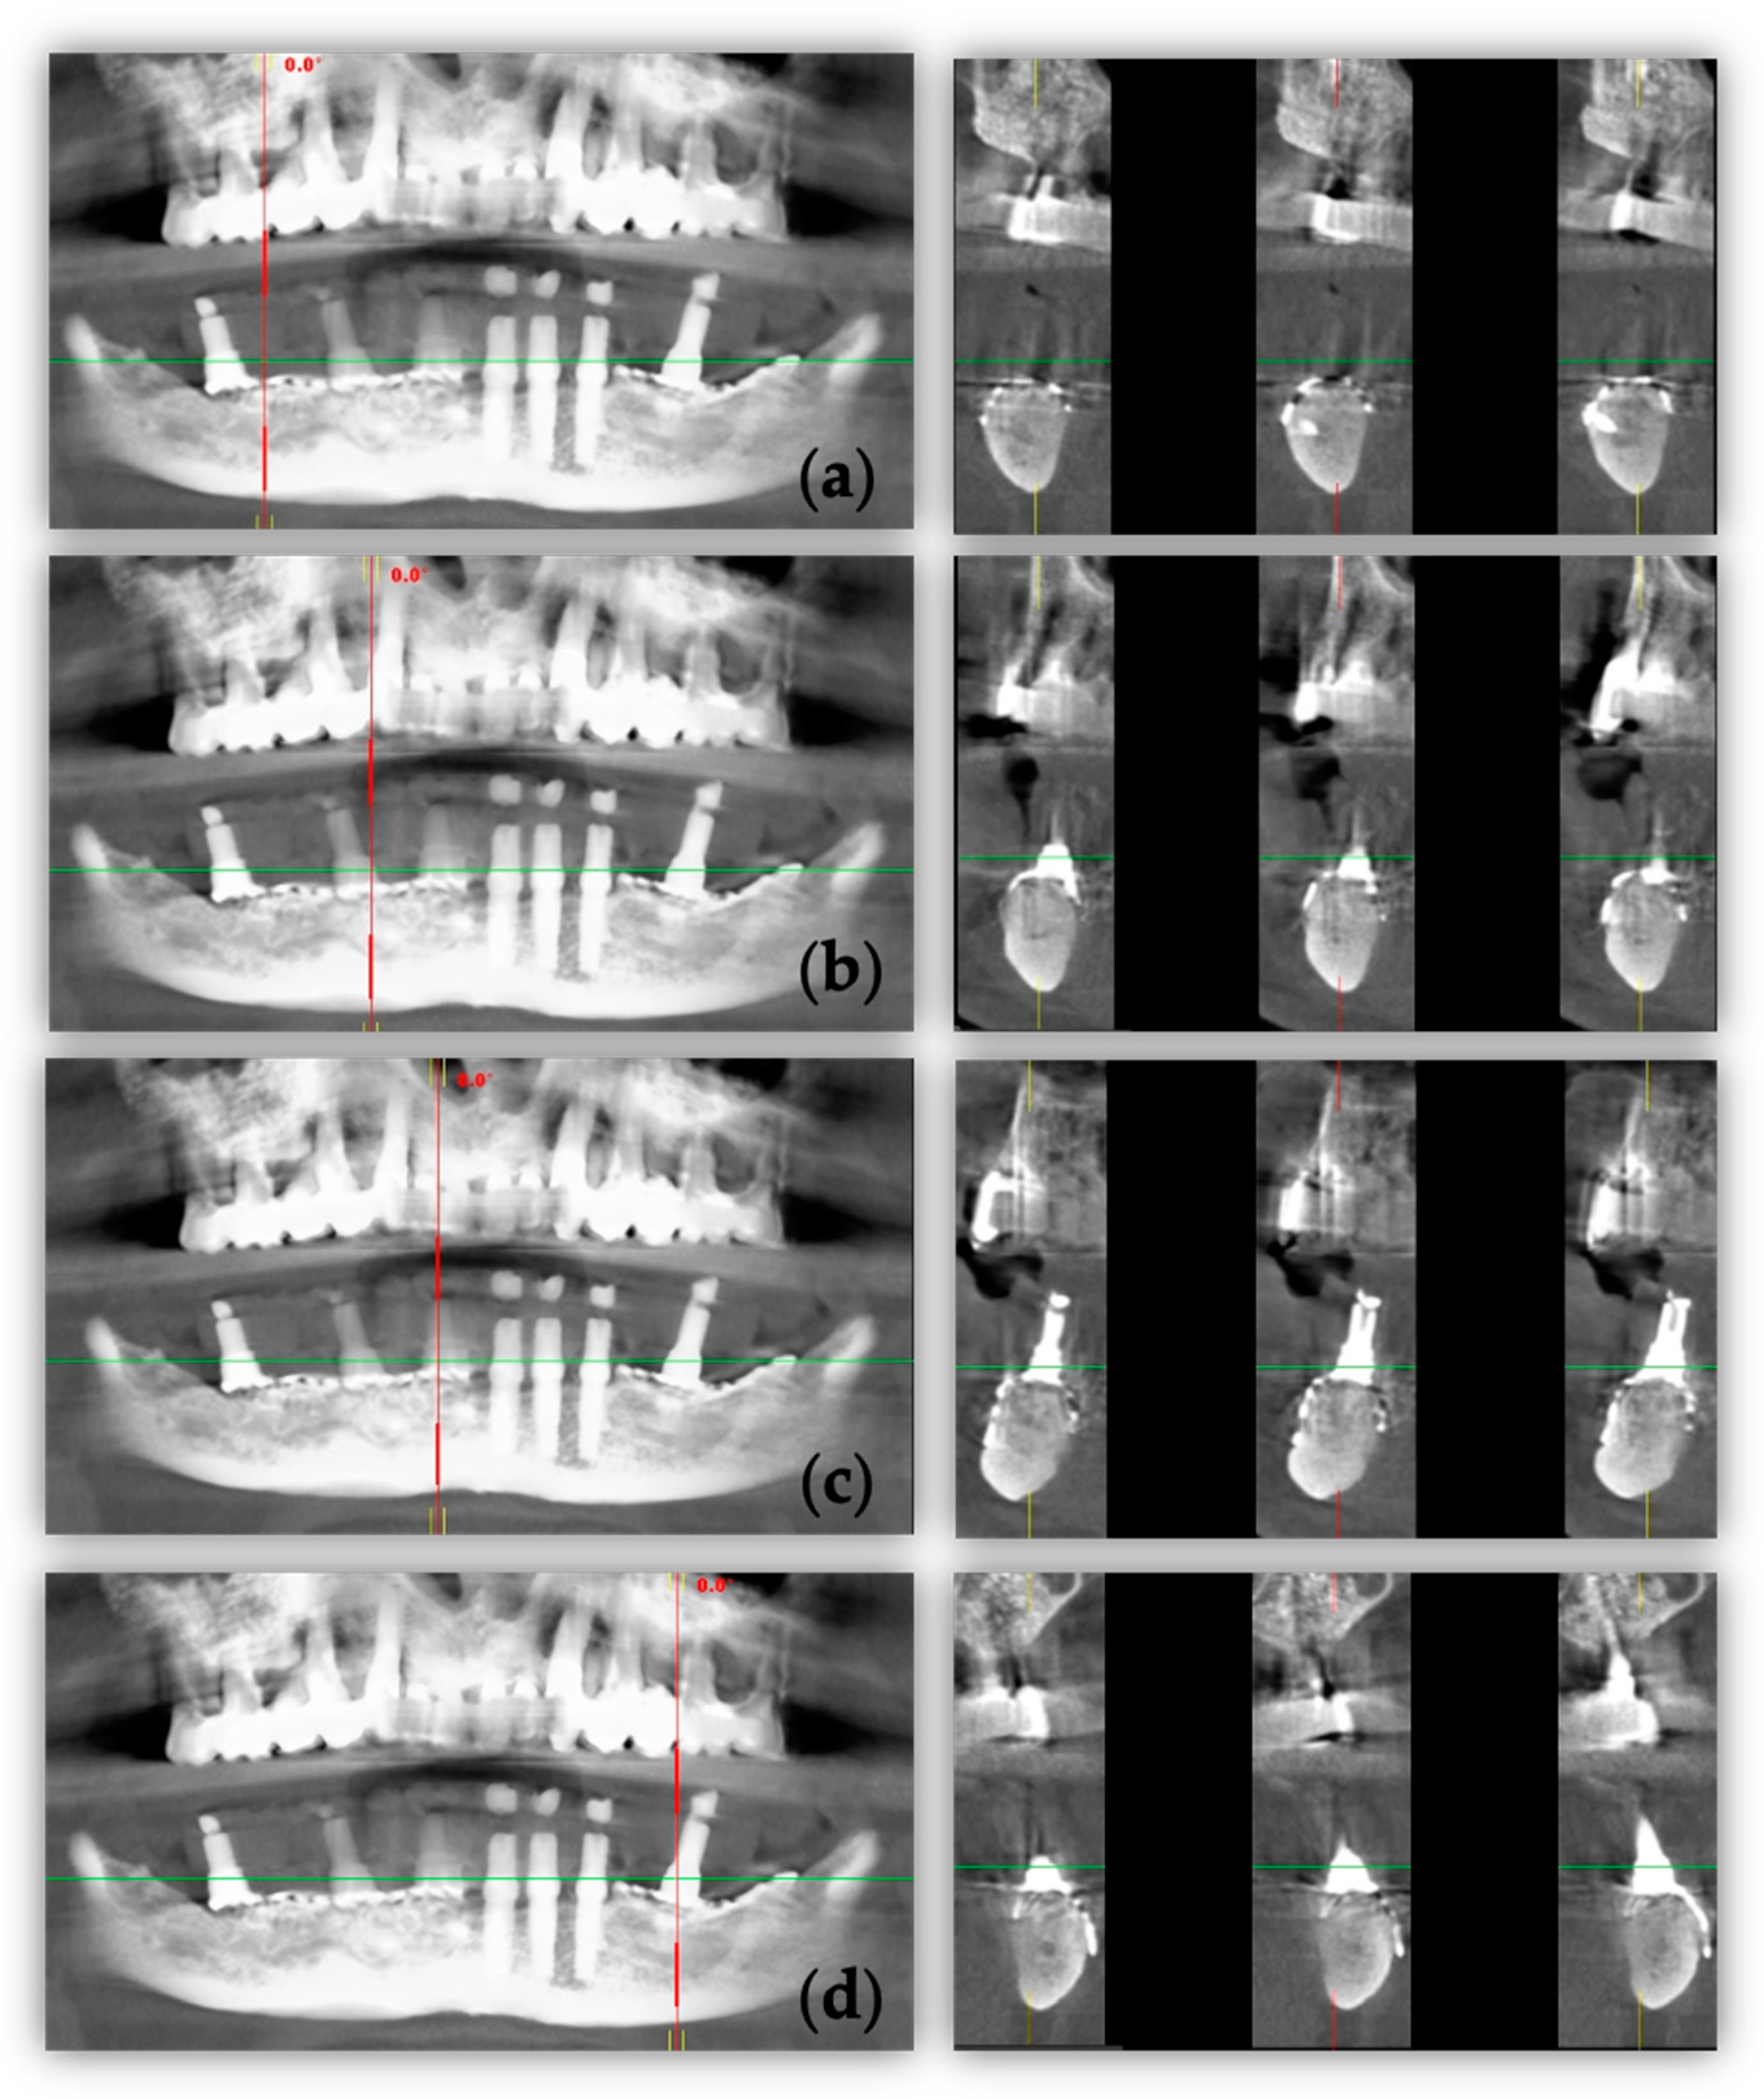

2. Case Report